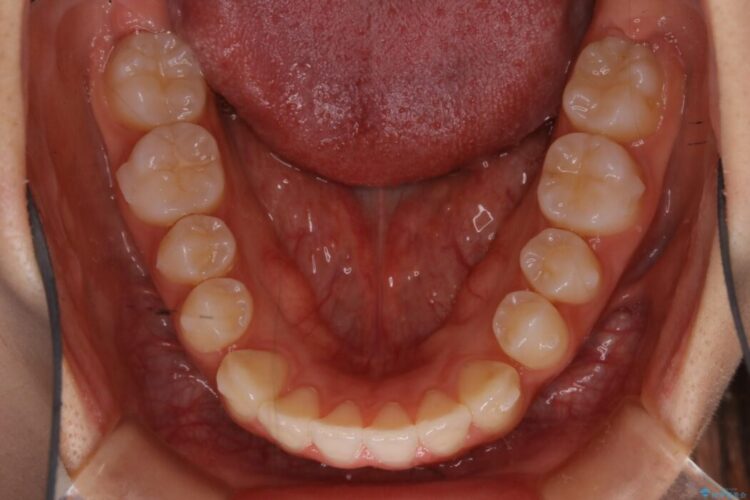

下の歯が上の歯より前に出ている受け口と前歯のガタガタ(叢生)について治療したいとのことで来院されました。

詳しく検査したところ、上顎の歯が舌側に倒れこんでしまっていることや歯列のガタガタなどにより口を閉じた時に上下の前歯の先端が接触してしまっていました。

よってまずは上顎の歯列を整えることから始め、前歯同士の衝突を改善してから、噛みこむ位置を本来あるべき後方へと調整することとしました。